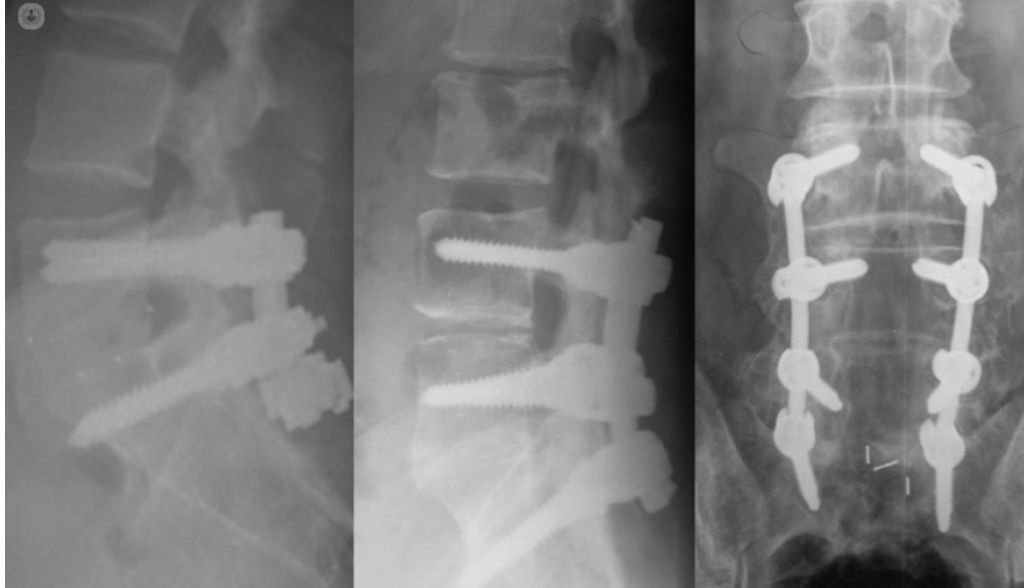

- Cifoescoliosis

Fotos y vídeos